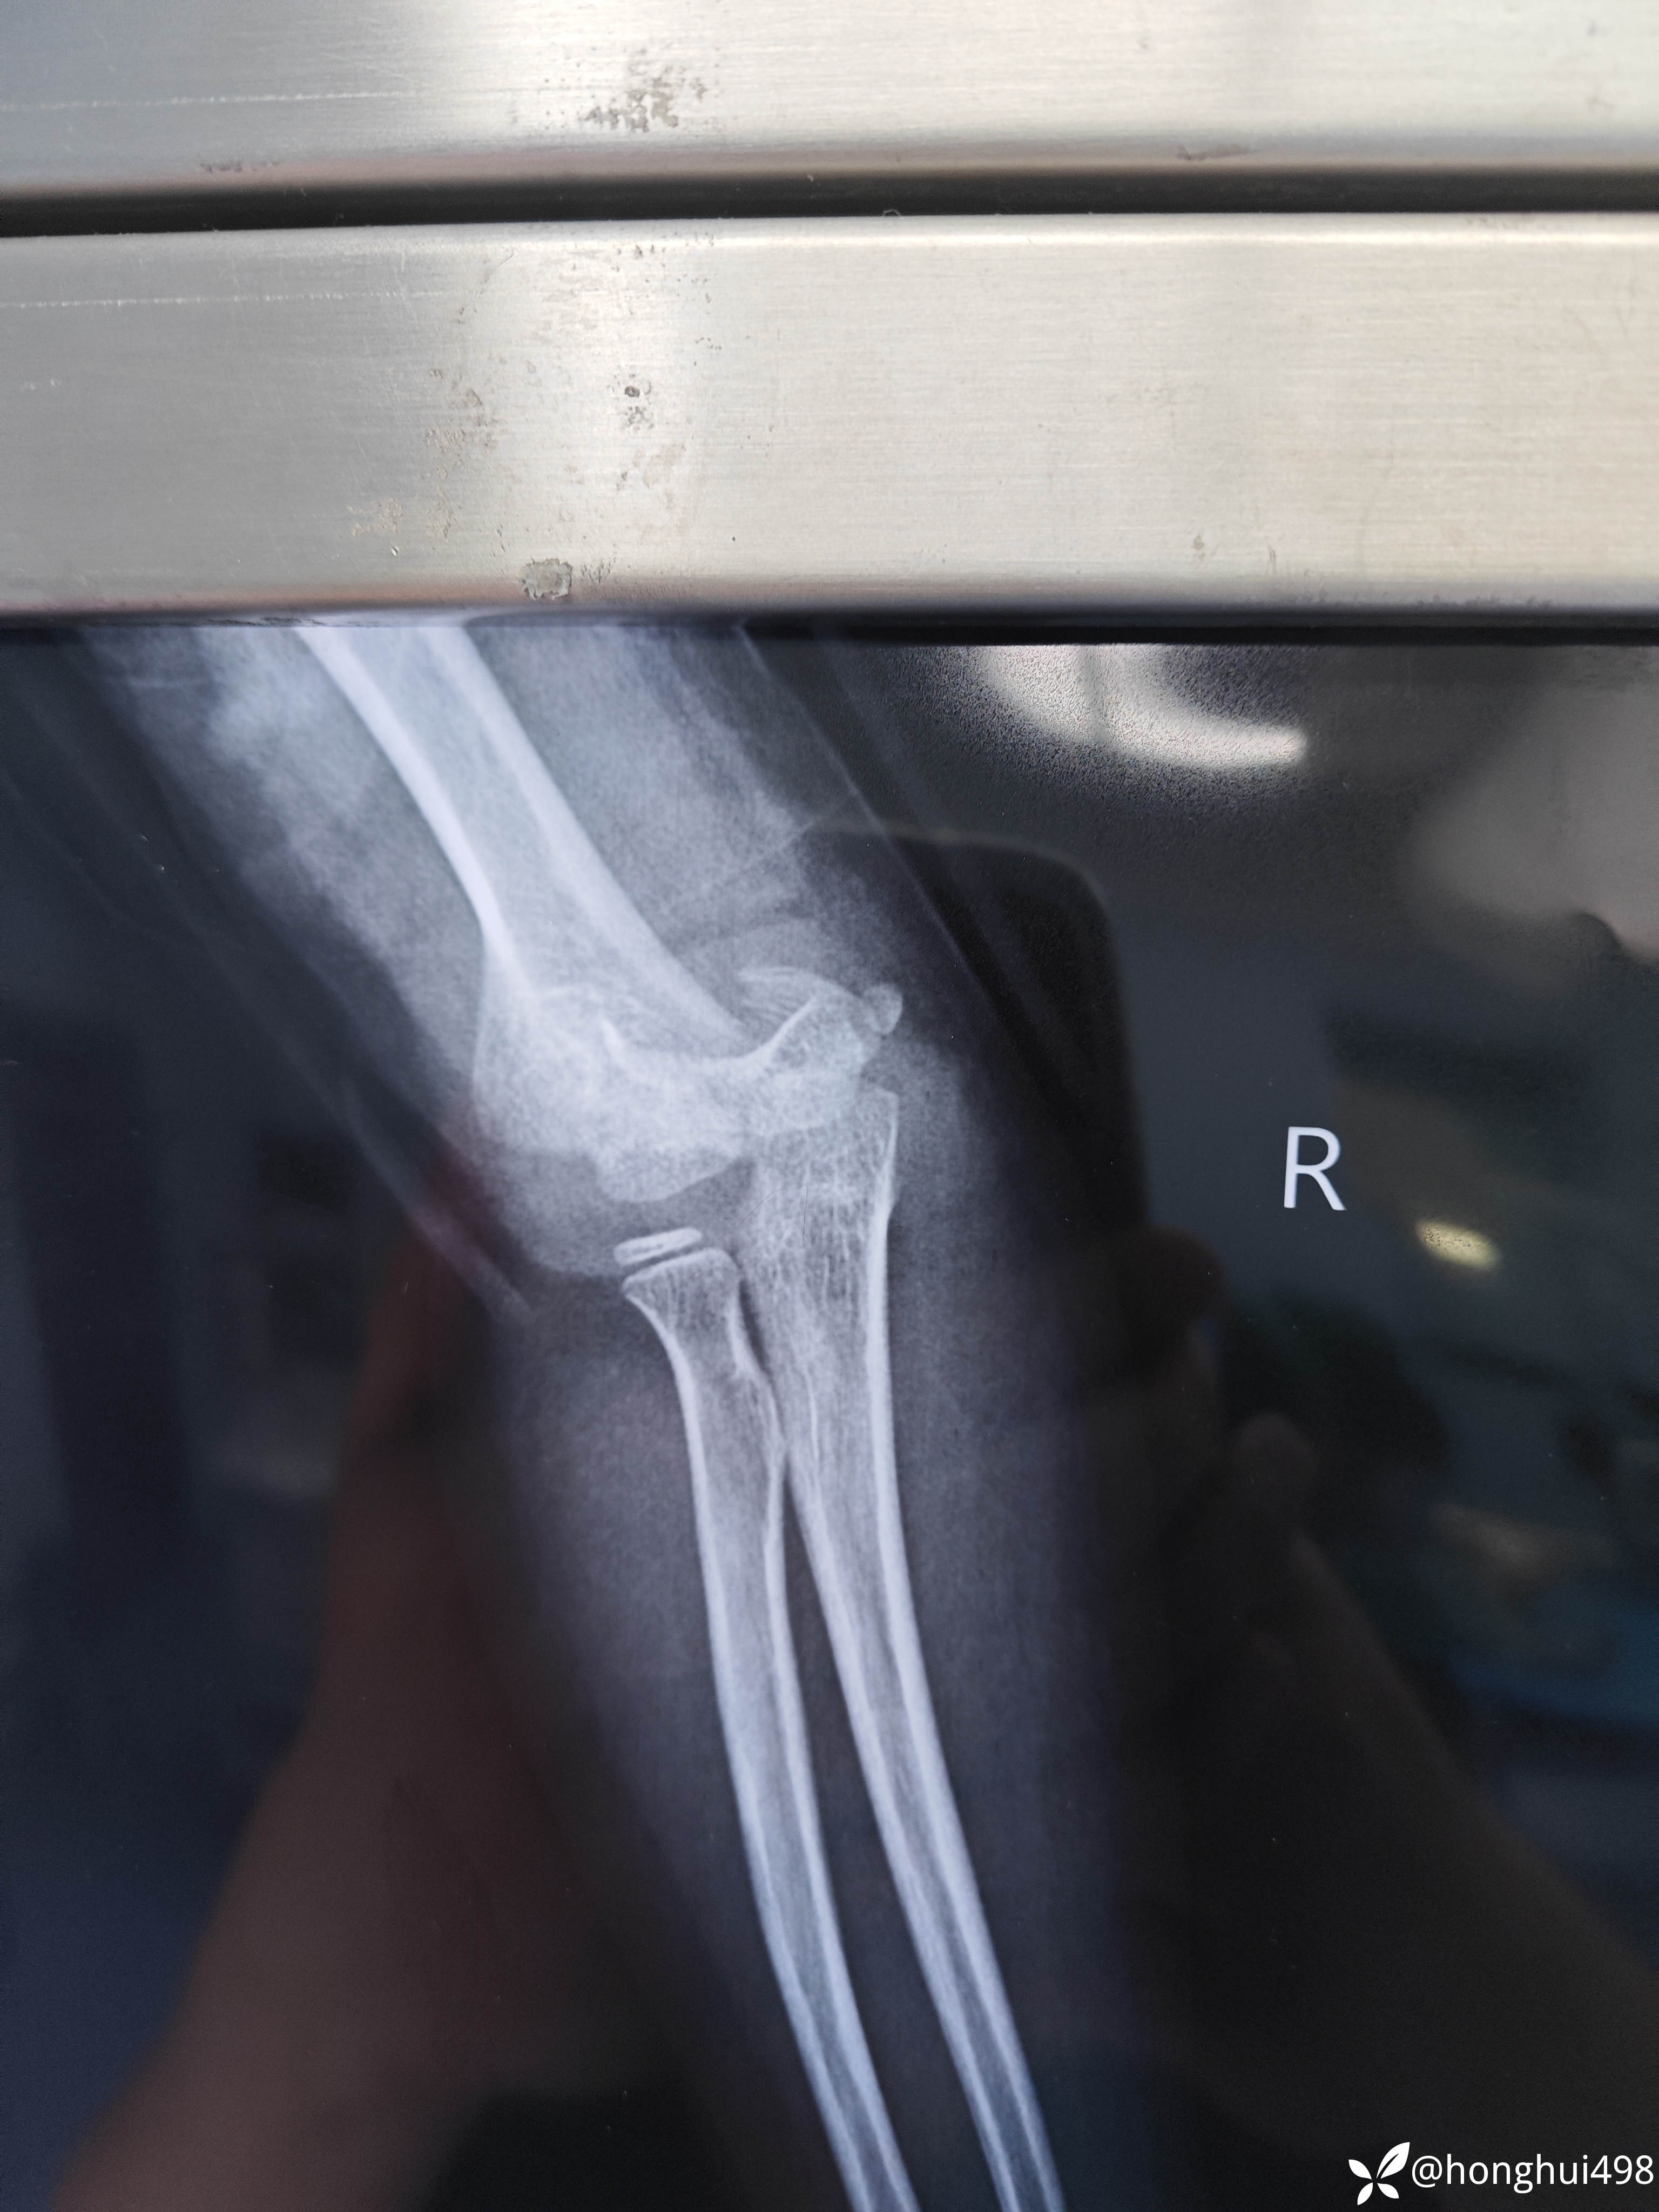

患儿女性,6岁,昨晚8点在家玩耍摔倒受伤,右肱骨髁上骨折。伤后在当地予手法复位草药外敷,伤后15小时来我院就诊,住院麻醉下闭合复位克氏针内固定。